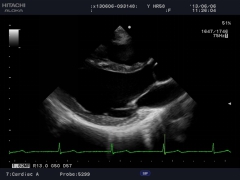

臨床圖例

FAM全方位M型

對于許多非正常體位的病人,醫(yī)生很難得到滿意的標準圖象,這對一些必要的測量如心功能測量會帶來一定的影響,為此,阿洛卡開發(fā)出任意角度M型,并同時可以取三條取樣線,其中每一條取樣線都可以任意改變角度,3600旋轉(zhuǎn),不需要選擇旋轉(zhuǎn)點。取樣既可在實時條件下進行,也可在凍結(jié)后完成。為用戶提供了非常便捷的方法。

TDI組織多普勒成像

TDI已成為重要的心臟功能評估技術(shù),能夠精確分析高幅、低頻多譜勒頻移及通過彩色編碼實時顯示心肌組織的運動速度。TDI能夠無創(chuàng)診斷心肌收縮、舒張的速度,進行左室收縮、舒張功能的評價,特別在舒張功能的評價方面,TDI能夠在收縮功能受累之前的心肌運動低下的病人得到早期的診斷,并得出沿室壁內(nèi)膜運動的速度,用以評價左室節(jié)段運動的狀態(tài),獲得高質(zhì)量的多譜勒信息,測出速度、平均速度和瞬間加速度等參數(shù)值。此項技術(shù)為臨床冠心病、心肌病、心律失常等多種疾病的診斷提供了可靠的診斷依據(jù)。